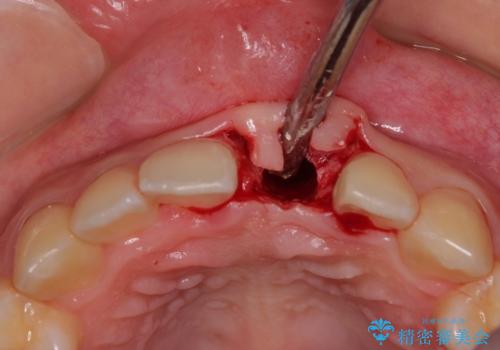

抜歯、インプラント埋入、仮歯の装着が同時に可能な1DAYインプラントを行いたいところでしたが、吸収による歯肉の炎症が著しいため、抜歯後に炎症が治まるまで待機し、極力早期にインプラント埋入を行うこととしました。

長い間歯肉が炎症を患っていたため、炎症改善後には歯肉がやや退縮した状態となっていました。

歯肉移植により歯肉形態を改善するプランも提案しましたが、十分な仕上がりとのことで、大変満足していただけました。